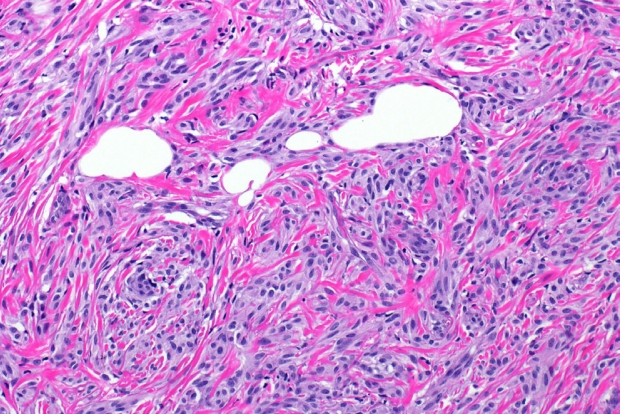

- Features on frozen section for schwannomas include a bland spindle cell proliferation with various degrees of cellularity (Fig. 2) [16,17]. Individual cells demonstrate anisonucleosis, and have wavy, elongated nuclei with tapering ends. These are arranged in parallel along the fibrillary and variably collagenous stroma. Hemosiderin deposition may also be present [17]. It is important to note that frozen artifact is often prominent, which includes cytoplasmic vacuolization and gaps between collagen. Nuclear freezing artifact may also lead to an incorrect impression of malignancy [18].

Fig. 2.Intraoperative frozen section of schwannoma demonstrating a spindle cell proliferation with Verocay bodies, and variable cellularity (Antoni A and B). Clear cell change and white gaps in tissue are due to frozen section artifact.